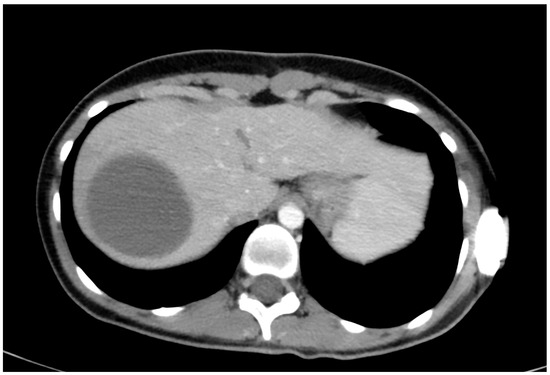

Rare Complication of Cardiopulmonary Resuscitation—Liver Injury

by David Hoskovec, Pavol Klobušický, Adam Pudlač, Matyáš Lochman, Zdeněk Krška and Petr Dytrych

Medicina 2024, 60(9), 1470; https://doi.org/10.3390/medicina60091470 - 9 Sep 2024

Background and Objectives: Liver injury is a rare complication of cardiopulmonary resuscitation. Correct and early diagnosis and treatment are essential. The clinical signs of injury may be masked by the cardiac arrest. We present a single-centre retrospective observational study of traumatic liver [...] Read more.

Background and Objectives: Liver injury is a rare complication of cardiopulmonary resuscitation. Correct and early diagnosis and treatment are essential. The clinical signs of injury may be masked by the cardiac arrest. We present a single-centre retrospective observational study of traumatic liver injury after cardiopulmonary resuscitation. Materials and Methods: A retrospective analysis of the patients treated for liver injury after cardiopulmonary resuscitation was conducted. Demographic data, the cause of resuscitation, the duration of restoration of spontaneous circulation (ROSC), and the surgical approach were analysed. Results: We have treated nine patients with severe liver injury after cardiopulmonary resuscitation. The diagnosis was made on the basis of cardiopulmonary instability, a fall in the erythrocyte count in eight cases, and was confirmed by CT or ultrasound examination. The last one was diagnosed accidentally on MR. Surgery, in cases of unstable patients, was followed immediately after a diagnosis. We combined liver sutures and intra-abdominal packing with a planned second-look surgery. Five of the nine patients survived. Conclusions: Liver injury after cardiopulmonary resuscitation is rare and is associated with high mortality. The recurrence of cardiopulmonary instability and/or a low or falling red blood cell count are the main signs of this injury. Bedside ultrasound and CT scans are the most important methods to confirm the diagnosis. The rule of surgical repair is the same as in all liver injuries, regardless of aetiology. The key factors for survival include early diagnosis, together with the length of restoration of spontaneous circulation (ROSC). Full article

Show Figures

Figure 1